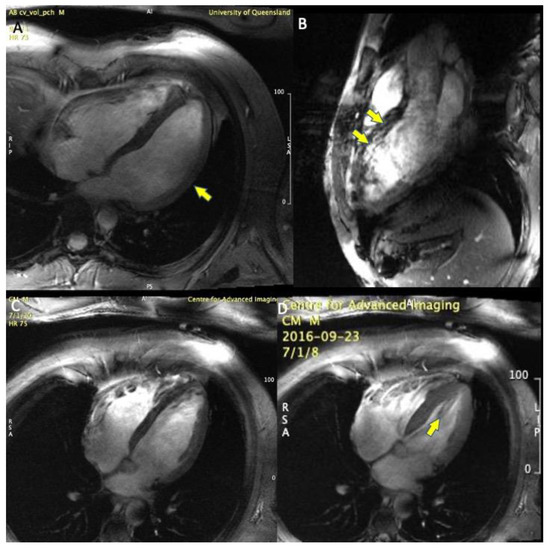

7-Tesla Functional Cardiovascular MR Using Vectorcardiographic Triggering—Overcoming the Magnetohydrodynamic Effect

2. Materials and Methods

3. Results